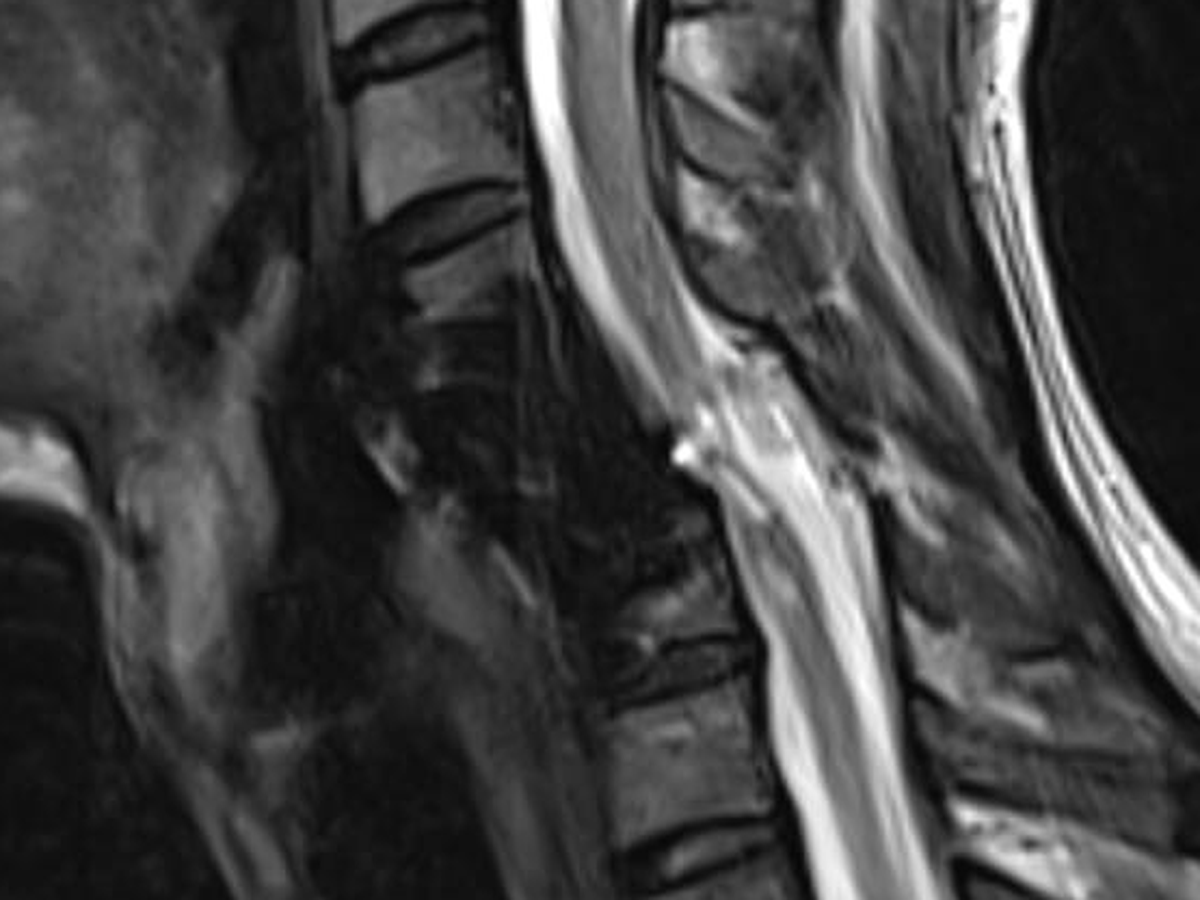

Probablemente escuchaste de mi caso, hace un año, me rompí el cuello lo que me provocó una fractura en la cervical 5, y por ese motivo, perdí la movilidad de mi cuerpo de los hombros para abajo y gracias a la operación que se me realizó estoy vivo,

tristemente la instrumentación de esta primera operación se movió, está presionando mi médula y mi cuello está en riesgo nuevamente al igual que mi vida.